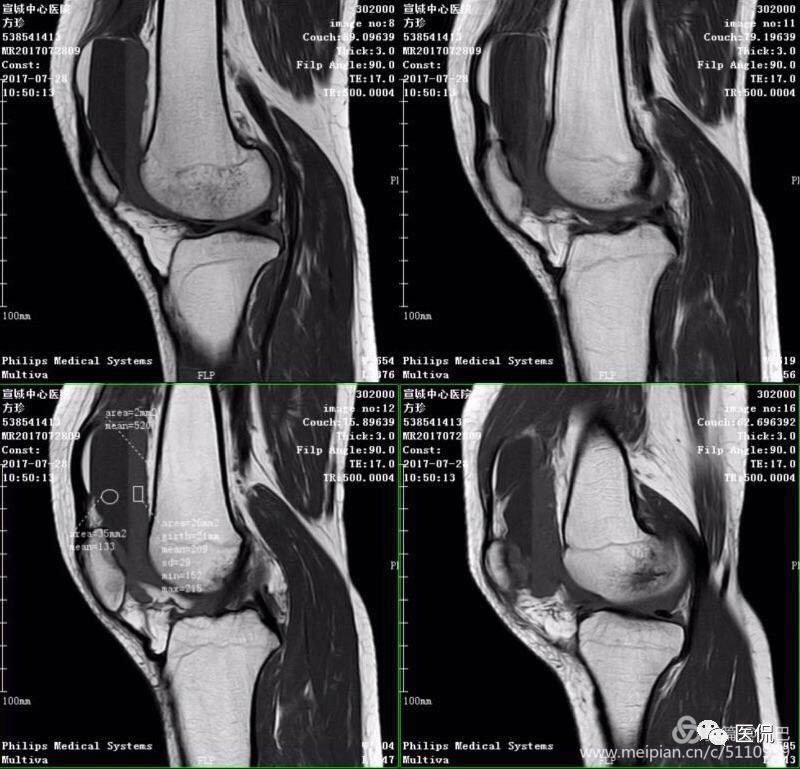

1、单液-液平面:上层呈短T1、长T2信号、T2压脂像低信号、Pd像呈高信号;下层呈中等T1、T2信号、T2压脂像和Pd像呈较高信号。

2、双夜-液平面:上层呈短T1、长T2高信号、T2压脂像低信号、Pd像呈高信号;中层呈长T1、长T2信号、T2压脂像和Pd像呈较高信号;下层呈中等T1、T2信号、T2压脂像和Pd像呈较高信号。

3、多液-液平面:最上层呈无信号区;上层呈短T1、长T2高信号、T2压脂像低信号、Pd像呈高信号;中层呈长T1、长T2信号、T2压脂像和Pd像呈较高信号;下层呈中等T1、T2信号、T2压脂像和Pd像呈较高信号。